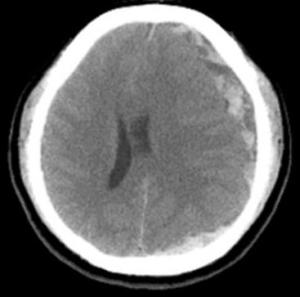

三、大腦出血的併發症:類似於中風。

8.根據病情,臨床表現,症狀,體徵選擇做心電圖,B超,X線,CT,MRI,生化等檢查。